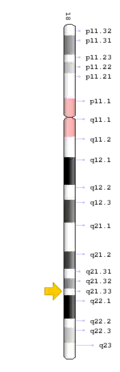

TCIRG1 mutation

The TCIRG1 gene is present in chromosome locus 11q13, which encodes for the a3 subunit of vacuolar H+ ATPase (V-ATPase) that is unique to osteoclasts.[12] The a3 subunit is responsible in anchoring the vacuolar proton pump to the ruffled membrane of osteoclasts.[9] The V-ATPase is important in mediating the transport of hydrogen ions into the resorption lacunae, which is a pit on the bone surface enclosed by the osteoclast for bone resorption. The accumulation of ions in the lacuna facilitates the decomposition of hydroxyapatite crystals by creating an acidic environment, resulting in bone resorption.[12]

TNFRSF11A mutation

The TNFRSF11A gene is present in chromosome locus 18q21.33, which encodes for the receptor activator of NF-κB (RANK).[13] RANK is expressed in immature osteoclasts, which facilitates osteoclasts maturation upon binding of RANK ligand (RANKL). Binding of RANK ligand mediates the RANK/RANKL/OPG signalling pathway. The pathway mediates osteoclast differentiation and activation by promoting differentiation of precursors into multinucleated osteoclasts, and activating osteoclasts, thereby contributing to bone resorption and remodelling. Health conditions related to genetic changes in TNFRSF11A includes osteopetrosis, osteolysis, and Paget's disease of bone.[14][15]

SLC29A3 mutation

The SLC29A3 gene is present in chromosome locus10q22.1, which encodes for the equilibrative nucleoside transporter 3 (ENT3), a nucleoside transporter that is present in membranes of mitochondria and lysosomes.[9] ENT3 is responsible for the trafficking of nucleoside, free purines and pyrimidines into the mitochondria and out of lysosomes.[9][16] Mutations in the gene is often accompanied by histiocytosis-lymphadenopathy plus syndrome, which is characterised by the accumulation of histiocytes leading to lymphadenopathy and other symptoms.[16]